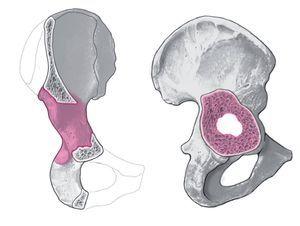

Figura 8. Fresado del centro acetabular con una fresa significativamente más pequeña que el componente retirado para obtener un nuevo centro acetabular. Para garantizar un mejor contacto de los bordes óseos con la prótesis acetabular en caso de un defecto segmentario, puede ser necesaria una medialización del centro acetabular obteniendo o aumentando un defecto acetabular central. Retirada del material fresado. Zona de contacto óseo para una fijación de tres superficies.

Figura 9. Se continúa el fresado de tamaño progresivo central sin presión hasta obtener una superficie ósea suficiente del acetábulo. Consejo: a menudo es necesario aumentar un defecto segmentario central a través de un fresado cuidadoso en profundidad con tal de obtener al final un soporte periférico suficiente a nivel del borde acetabular. En caso de defectos segmentarios se ha de tener en cuenta que se obtenga en tres zonas el suficiente contacto óseo para conseguir el anclaje press-fit (por regla general, inferior a nivel de la incisura acetabuli, anterior o anterosuperior, y posterior o posterosuperior). Para asegurar una suficiente superficie triplanar, en ocasiones es necesario debilitar el reborde preexistente para preservar el aspecto posterior.

Figura 10. Colocación del hueso fresado en el suelo acetabular y ocasionalmente en el defecto acetabular preexistente (lo último a menudo no es necesario). Introducción de un componente acetabular de pared fina de una talla superior a la de la última fresa, con lo cual se obtiene en las superficies de contacto un pressfit de 4 mm.